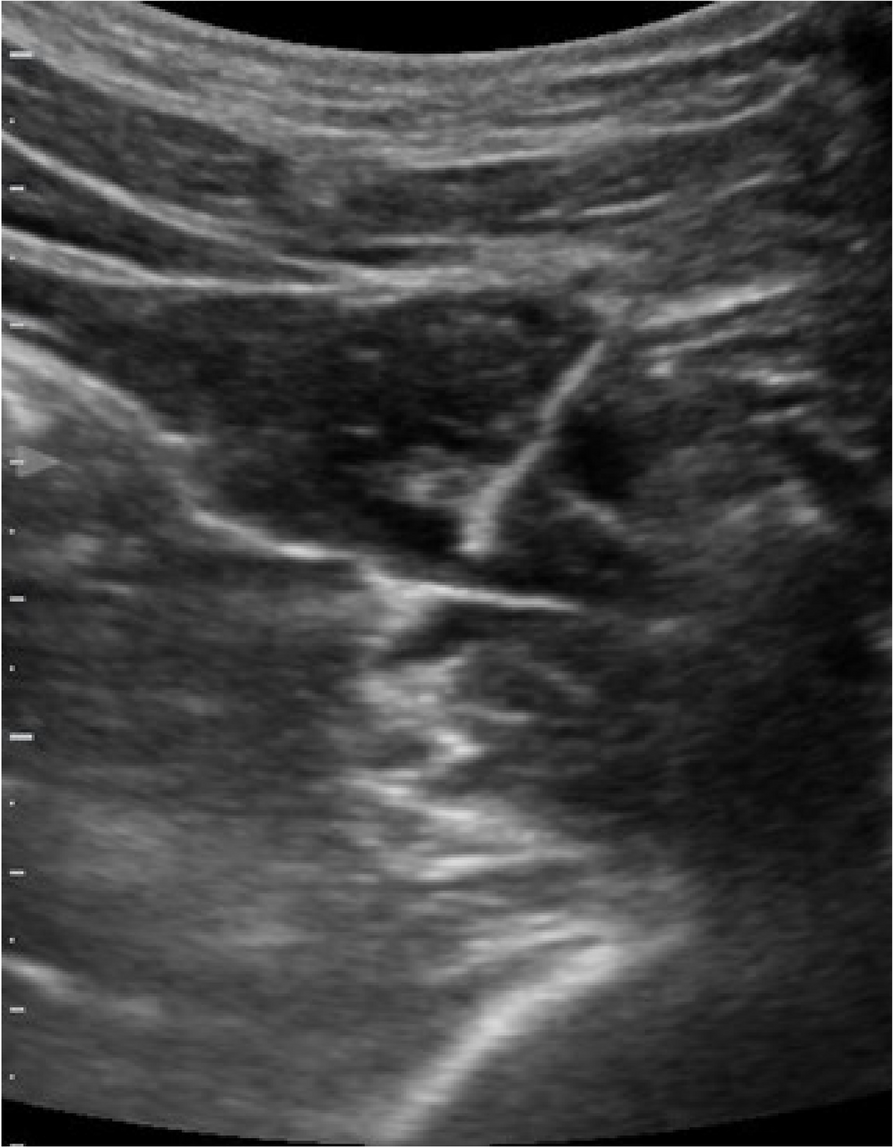

A few hours after the admission in ICU he reported a blunt abdominal pain, mainly on the right side, nausea and the exams showed increased amylase levels, urologists excluded any surgical involvement of pancreatic tissue and suspected a transient sphincter of Oddi dysfunction [3]. After one night in ICU he was transferred to the urology ward due to his clinical stability, even though Amylase peaked at 2340 U/l. Two days later abdominal pain increased to severe, with characteristics of peritonism and increased inflammatory markers. An abdomen-thorax CT scan revealed acute pancreatitis (AP) (Figure 1) and he was transferred to ICU. He started a standard treatment for acute pancreatitis and antibiotic therapy [4].

Fig. 1 (abstract A21).

See text for description